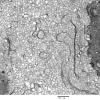

PERIPHERAL NEUROPATHY

0 PNS ARTIFACTS (8)